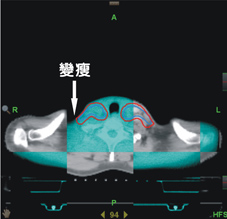

另外在影像導影系統下,我們發現每日位移量最多可達1cm,仍然超出傳統強度調控放射線治療計畫之添加距離範圍(如:圖三)。故導航螺旋刀治療患者,透過每日影像導影系統進行每日治療位置之校正,截至目前案例,並無邊緣治療失敗之個案。反觀傳統強度調控放射線治療,其邊緣治療失敗占了失敗案例中的52%,此邊緣治療失敗的原因對於傳統強度調控放射線治療較差的局部控制與較差的存活率上,亦造成一定程度之影響。

圖三、影像導引系統可提前發現病人體態變化而做出修正